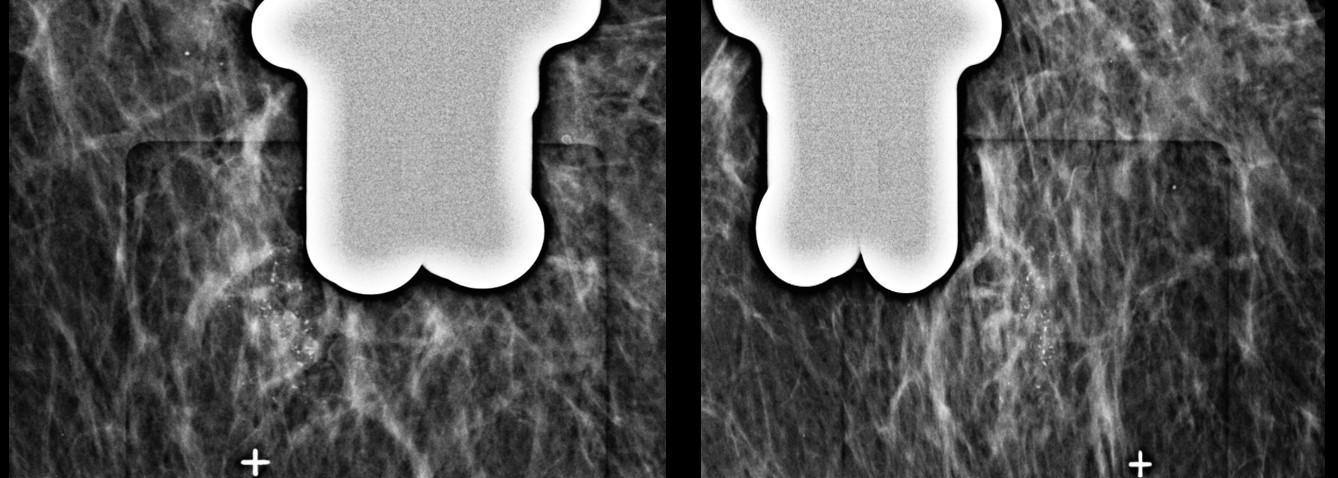

Realizado a análise do menor trajeto para acessar a área referida, a paciente foi posicionada em oblíqua, através da entrada de raios X em médio-lateral com angulação de 50°. As marcações dos alvos foram feitas em duas abordagens distintas (imagens 3 e 6), com objetivo de atingir a maior quantidade de microcalcificações. O procedimento foi realizado sem intercorrências e os fragmentos obtidos foram submetidos a um estudo radiológico demonstrando espécimens adequados com a presença de microcalcificações na amostra (imagens 5 e 7). O resultado anátomo-patológico obtido foi de carcinoma ductal in situ.